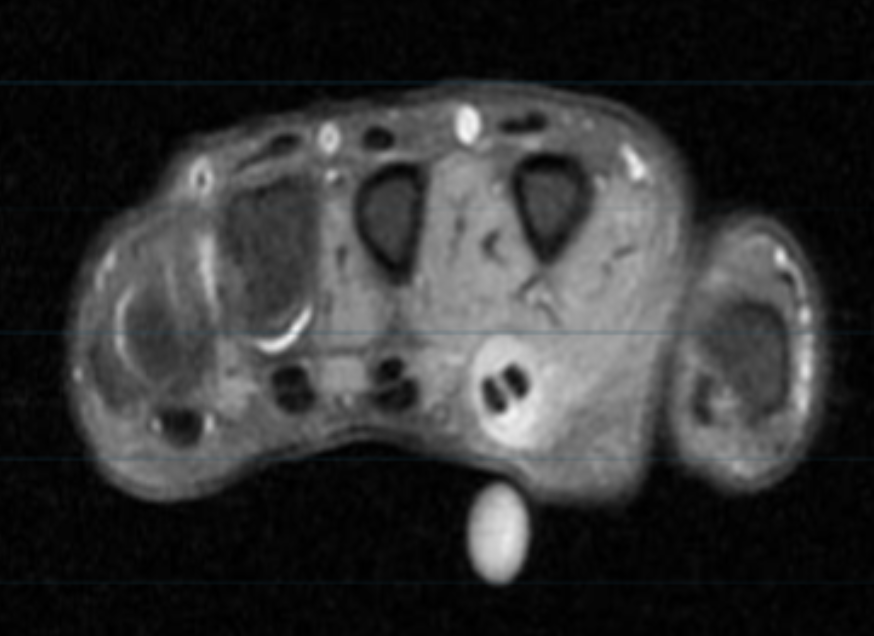

Describe the pathology (Ax T2 FS).

Tenosynovitis